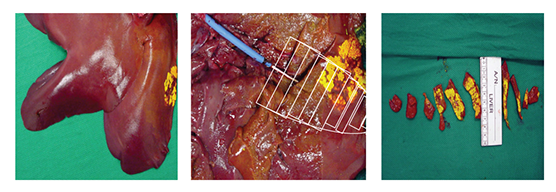

Serum samples were taken from the with­drawal syringe, right ventricle, aorta, and femoral vein at 10-minute intervals during and 30-minute intervals after infusion. Yellow tissue-marking dye was infused to mark the distribution of the 30-minute infusion (Figure 2). Blood serum samples and frozen tissue sections from the target liver site, waste, heart, and distal liver sites were analyzed with high-pressure liquid chromatography (HPLC).

Figure 2 Yellow tissue-marking dye showing the targeted area and the tissue-sampling demarcation.